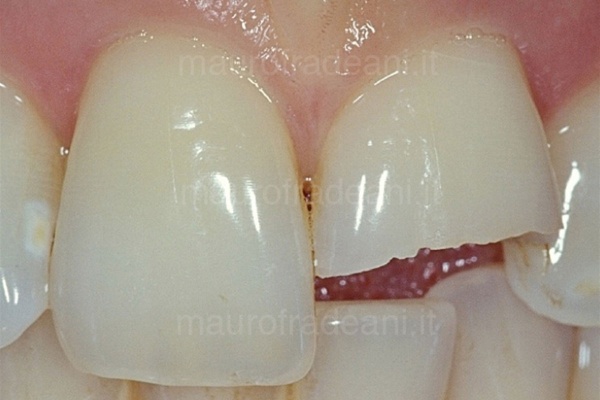

1/2: A severe trauma resulted in the fracture of a large portion of the left upper central incisor.

2/2: Together with the patient, the clinician decided to use composite material for this extensive restoration. Only one session is needed for this type of operation. The esthetic result achieved is particularly satisfactory.